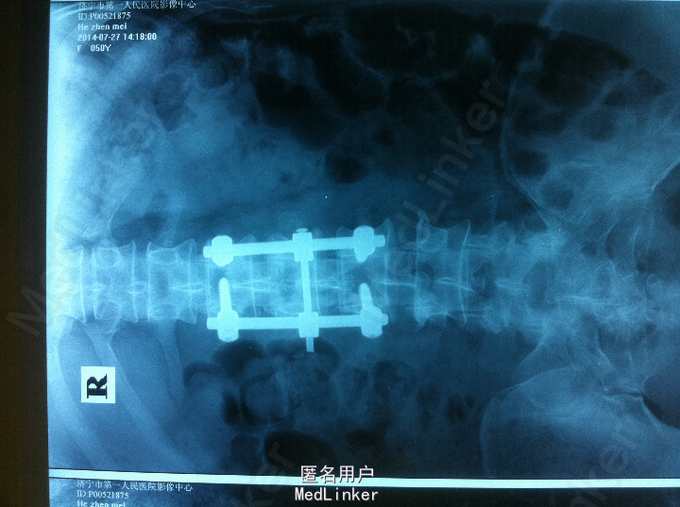

高处摔伤腰部疼痛、活动受限1入院。 中年女性,既往健康; 患者1天前从3米高处摔伤,臀部着地,及感腰部疼痛、活动受限,双下肢无放射性疼痛、麻木,双下肢活动可。

PE:腰部轻度后凸,叩痛,双下肢感觉无减退,双下肢肌力4-5级,巴氏征 阴性。 X-ray:腰2椎体骨折 CT:腰2椎体骨折,椎体后缘不连续 MR:腰2椎体骨折,腰2-3椎体水平硬膜外血肿

诊断:腰椎骨折 腰椎硬膜外血肿 处理:腰椎后路撑开复位内固定

术后1个月,患者轻度腰痛,双下肢感觉无减退,双下肢肌力5级 术后3个月,患者无明显腰痛,双下肢感觉、肌力正常 讨论:1、腰椎骨折累及中柱,无神经损伤表现,是否必须行椎板减压 2、外伤性硬膜外血肿,无神经损伤表现,是否有椎板减压指征